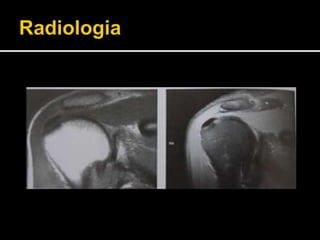

 TC e RNM: podem auxiliar no diagnóstico (?)

 2 tipos de aparência radiológica:

 Tipo 1: na fase aguda ou reabsorvida, em que não há

delimitação precisa das bordas do depósito.

 Tipo 2: na fase subaguda ou crônica, em que ocorre

homogeneidade na densidade do depósito e as bordas são

bem delimitadas.

 TC eRNM: podem auxiliar no diagnóstico (?)  2 tipos de aparência radiológica:  Tipo 1: na fase aguda ou reabsorvida, em que não há delimitação precisa das bordas do depósito.  Tipo 2: na fase subaguda ou crônica, em que ocorre homogeneidade na densidade do depósito e as bordas são bem delimitadas.